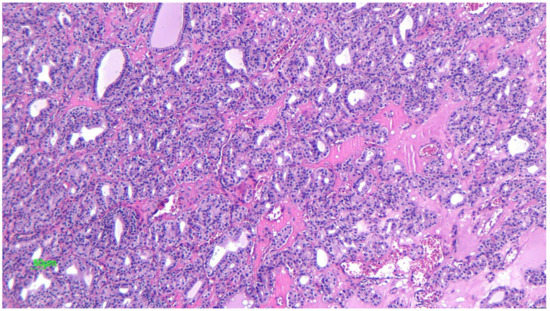

2.1. Dysgerminoma

2.1.2. Microscopic Features